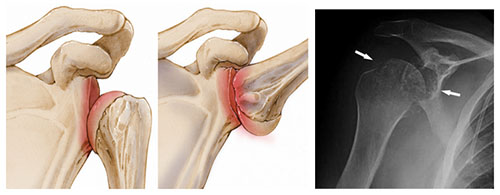

Подвывих плечевого сустава

Подвывих плеча представляет собой состояние, при котором плечевой кости происходит смещение от суставной впадины лопатки (вперед или назад) во время движений, связанных с наружной ротацией или отведением руки, что может произойти как при активных спортивных занятиях, так и в результате неловких движений в повседневной жизни. Для плечевого сустава характерна высокая вероятность развития суставной нестабильности, что связано с деградацией суставного хряща на головке плеча и образованием на ее задней поверхности дефекта Хилл-Закса. Обычно пациенты могут самостоятельно исправить вывихи, выполняя определенные движения.

Симптомы подвывиха плечевого сустава

Подвывих плечевого сустава характеризуется резкой или колющей болью в области плечевого сустава. Кожа над суставом становится красной, отекает и ощущается горячей на ощупь. Пациент может испытывать жжение в этой зоне. Поднять руку или выполнить движения в любом направлении становится затруднительно или даже невозможно.